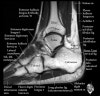

발목 관절의 MRI 단면 영상

- Axial section

Axial PD fat suppression evaluates the tendons and ligaments of the ankle particularly after acute/subacute injuries. It also is sensitive to talar dome osteochondral defects. Alternatively, a T2 sequence can be used to eliminate magic angle artifact that may occur as the tendons travel around the malleolar turns.

Tibiofibular ligaments

Lateral ankle ligaments

Deltoid and spling ligaments

Tendon(Achilles, Medial, Lateral, Anterior)